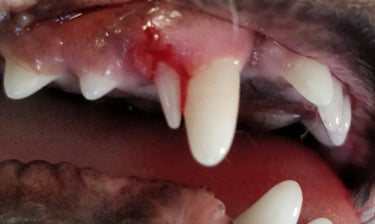

Tandonderzoek - Oroscopie - Tandbehandeling

Zoals bij de mens is de tandverzorging van uw huisdier uiterst belangrijk. Behandelingen worden onder algemene verdoving uitgevoerd.

tandsteen verwijderen

tandextractie

radiografie

endoscopie

Welke onderzoeken/behandeling het meeste geschikt zijn voor uw huisdier wordt geval per geval besproken.